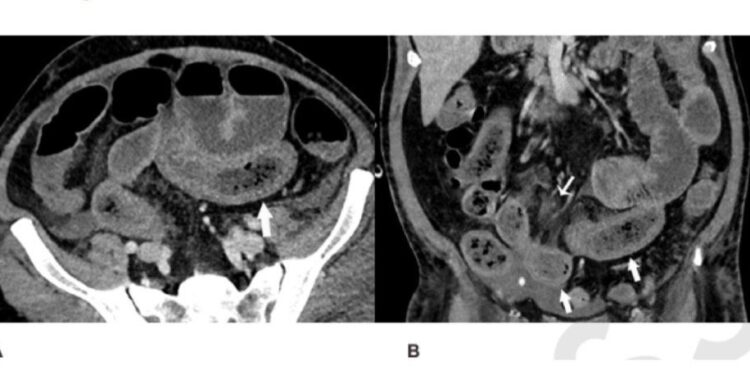

Una tomografía computarizada del abdomen y la pelvis de un hombre de 57 años sospechoso de tener un suministro de sangre deficiente en el intestino. La exploración muestra que su intestino delgado estaba distendido y engrosado en partes. Foto: Radiological Society of North America

Los hallazgos, publicados en la revista Radiology, mostraron signos de anomalías y problemas intestinales, y el flujo de bilis fue común en los escaneos de los pacientes. Alrededor de 31 por cientos de los escaneos mediante tomografías computarizadas mostraron que los pacientes tenían problemas en la pared intestinal.

También se encontró que los pacientes tenían padecimientos como el engrosamiento de la pared intestinal, así como quistes de gas en dicha pared y en la vena que lleva la sangre del tracto gastrointestinal y del bazo hacia el hígado. Uno de los pacientes presentaba una perforación intestinal. En 20 por ciento de los pacientes en cuidados intensivos, había signos de que el suministro de sangre a los intestinos era inadecuado.

“Algunos de los síntomas son típicos de la isquemia intestinal o necrosis del intestino, y en las personas sometidas a cirugía pudimos ver pequeños trombos vasculares junto a las áreas de necrosis intestinal.